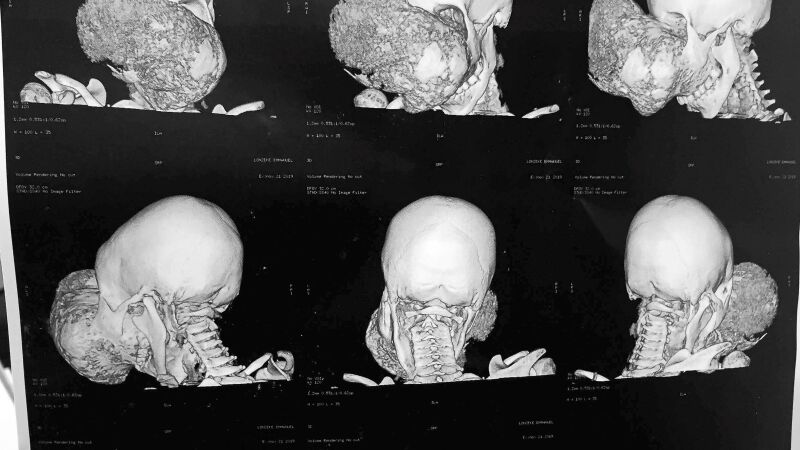

Emmanuel sufría un fibroma osificante gigante de base de cráneo y llegó a la Fundación Cavadas a través de una entidad que tiene una clínica en el Congo y no podía abordar una intervención tan compleja ya que el tumor, que seguía creciendo, le impedía ver y hablar.

Durante la primera intervención, que duró cerca de diez horas, se le quitó todo el maxilar, la zona entre las órbitas oculares, el paladar y una parte del interior de la boca, que fue reconstruido tras extirpar el tumor. La segunda cirugía, también de cerca de diez horas de duración, se centró en hacer la parte intracreaneal, para quitar la base anterior y media del cráneo y reconstruírselo con parte de sus propias costillas.